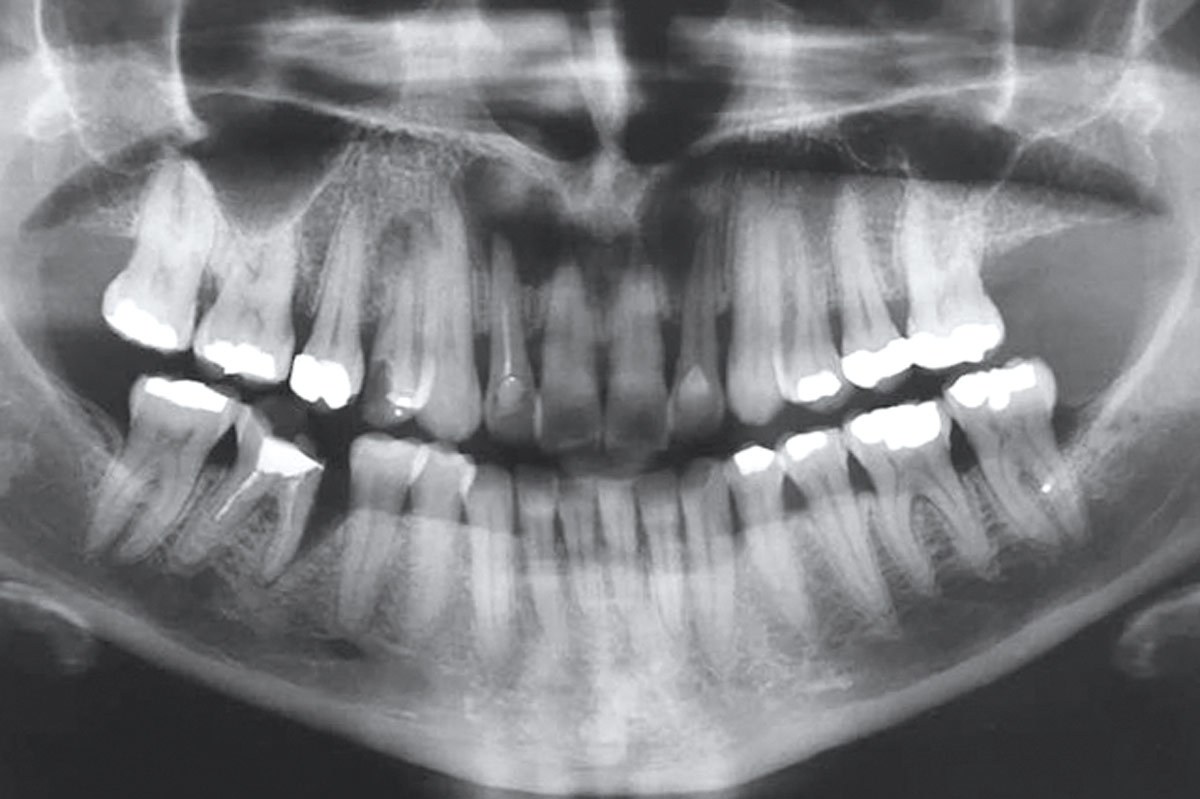

1/19 - Initial Orthopantomograph X-Ray

Immediate implant placement using maxresorb® - Dr. Alejandro Signorio